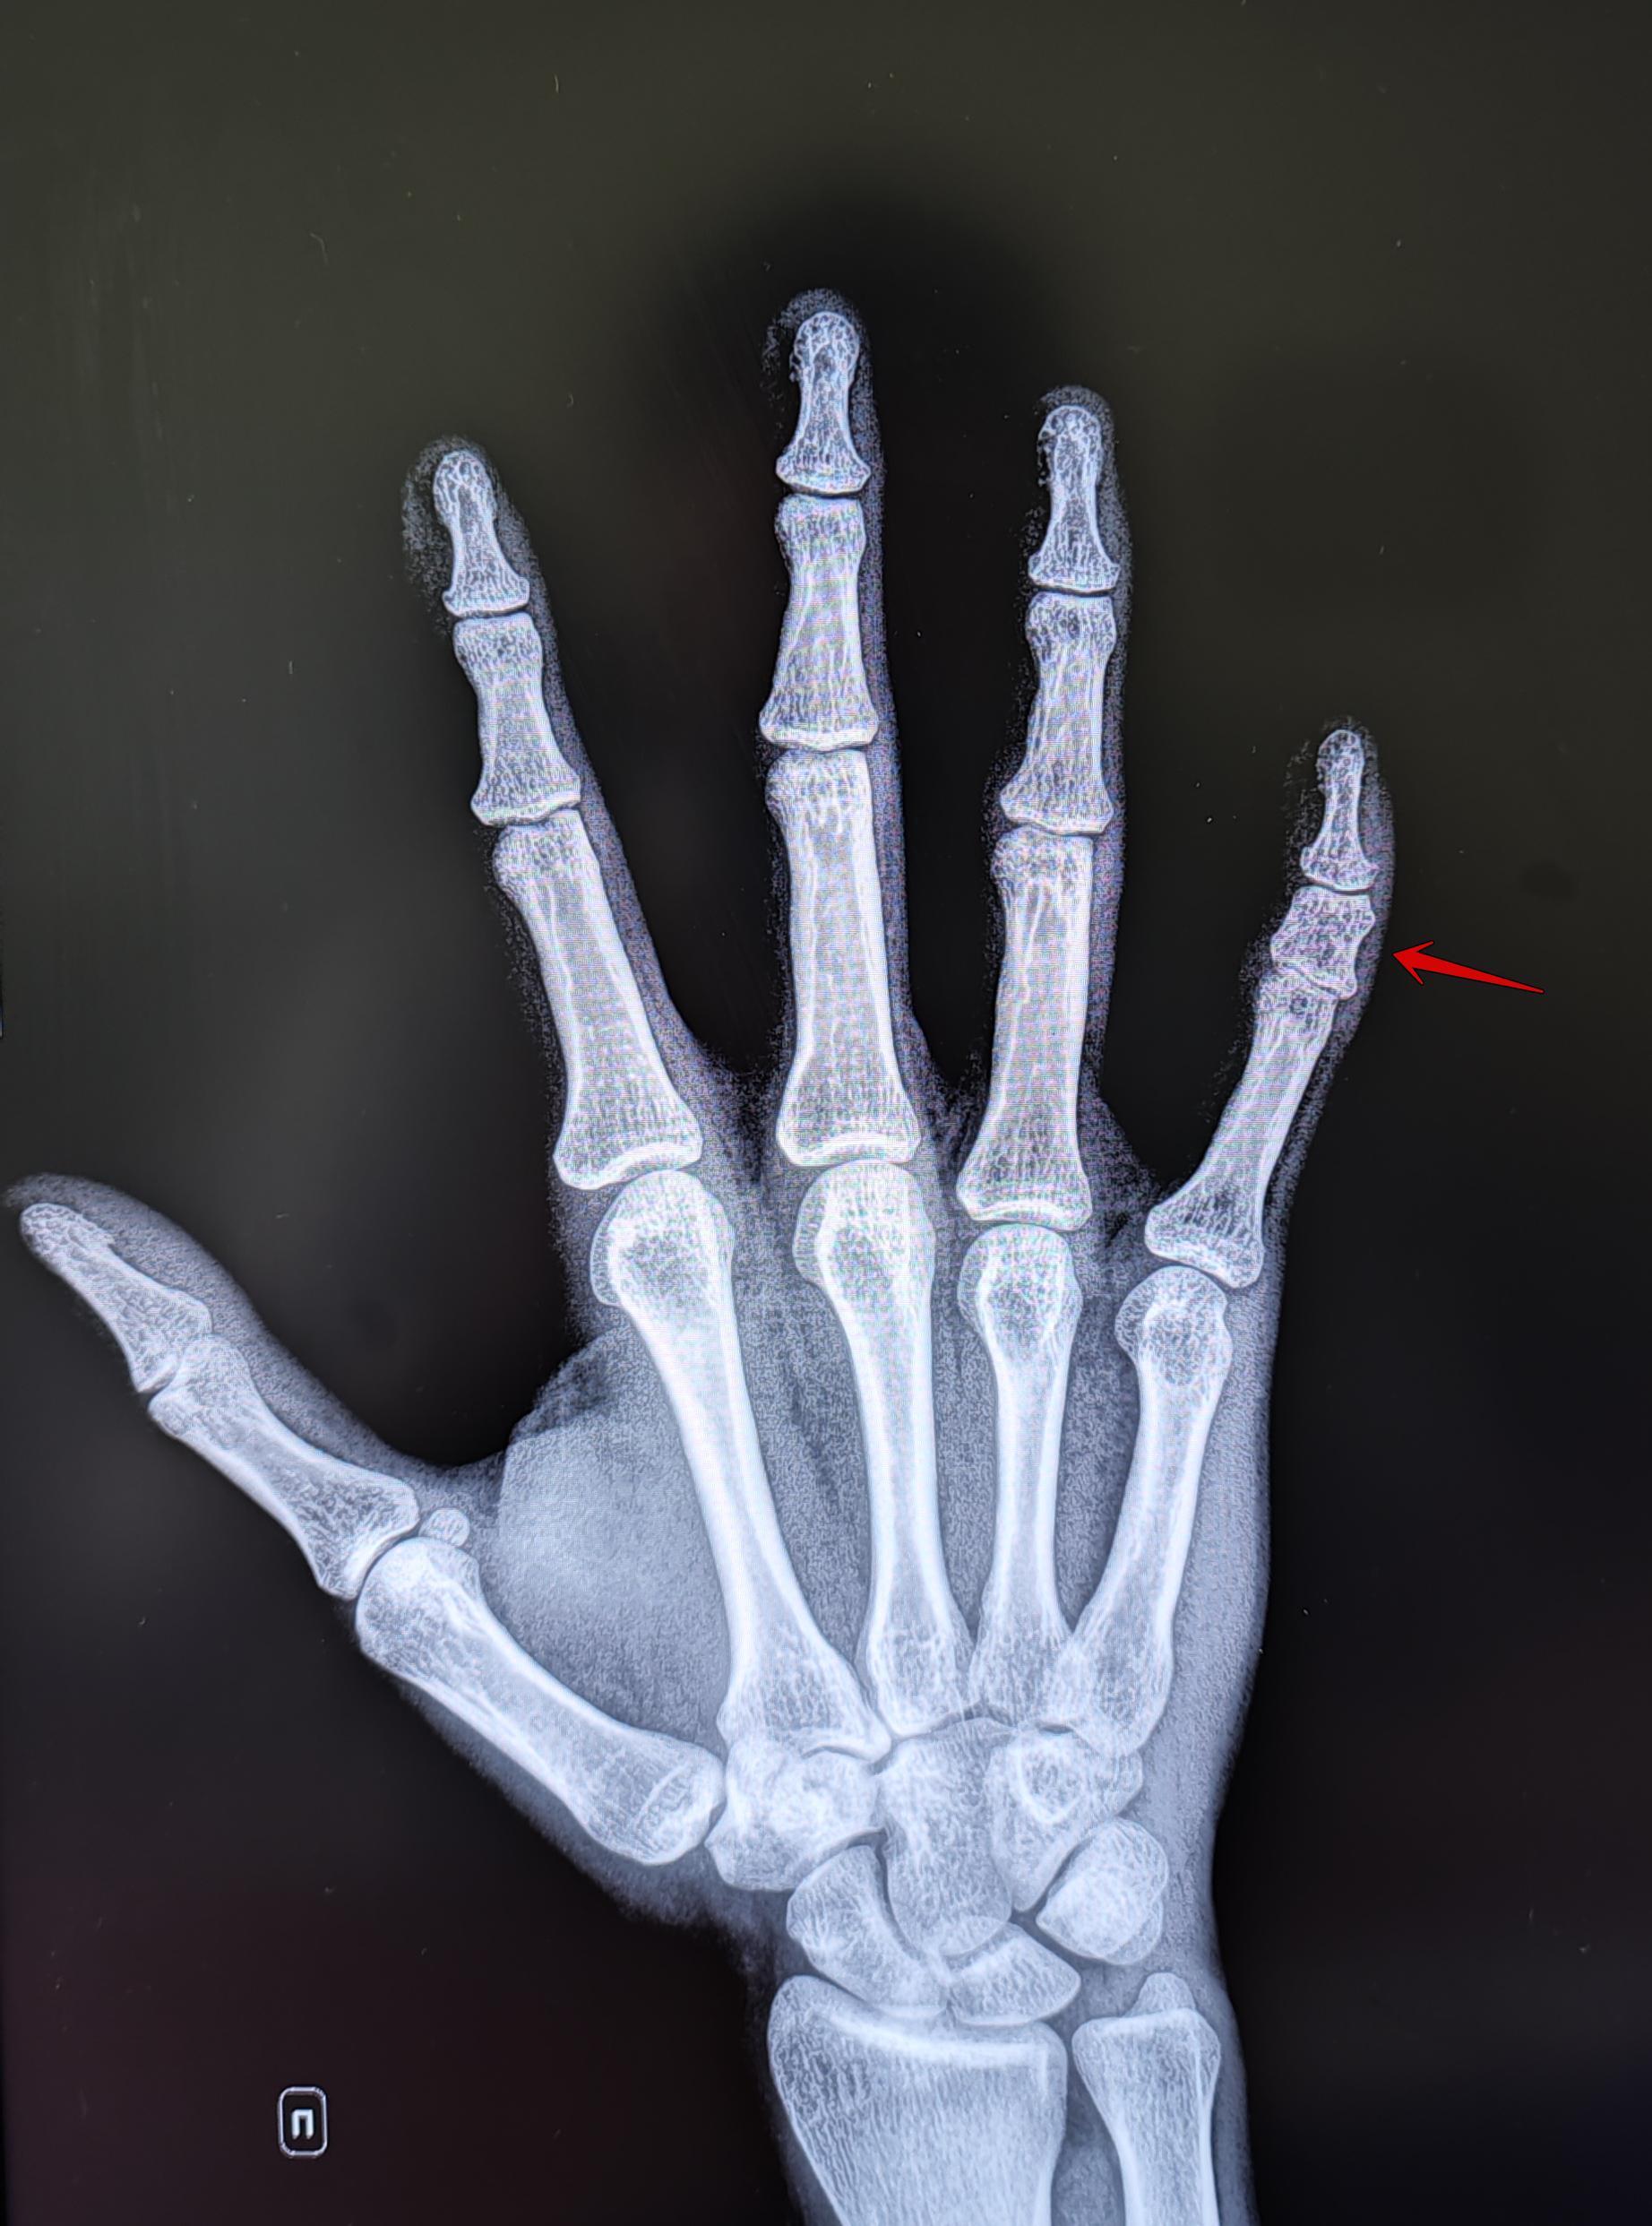

На Р-граммах правой кисти в 2х проекциях: травматических, деструктивных изменений не выявлено. Структура костной ткани не изменена. Средняя фаланга пятого пальца укорочена, утолщена. По остальным отделам кисти-без явной костной патологии.

Заключение: Врожденная аномалия развития правой кисти- брахидактилия (брахифалангия) средней фаланги пятого пальца правой кисти.